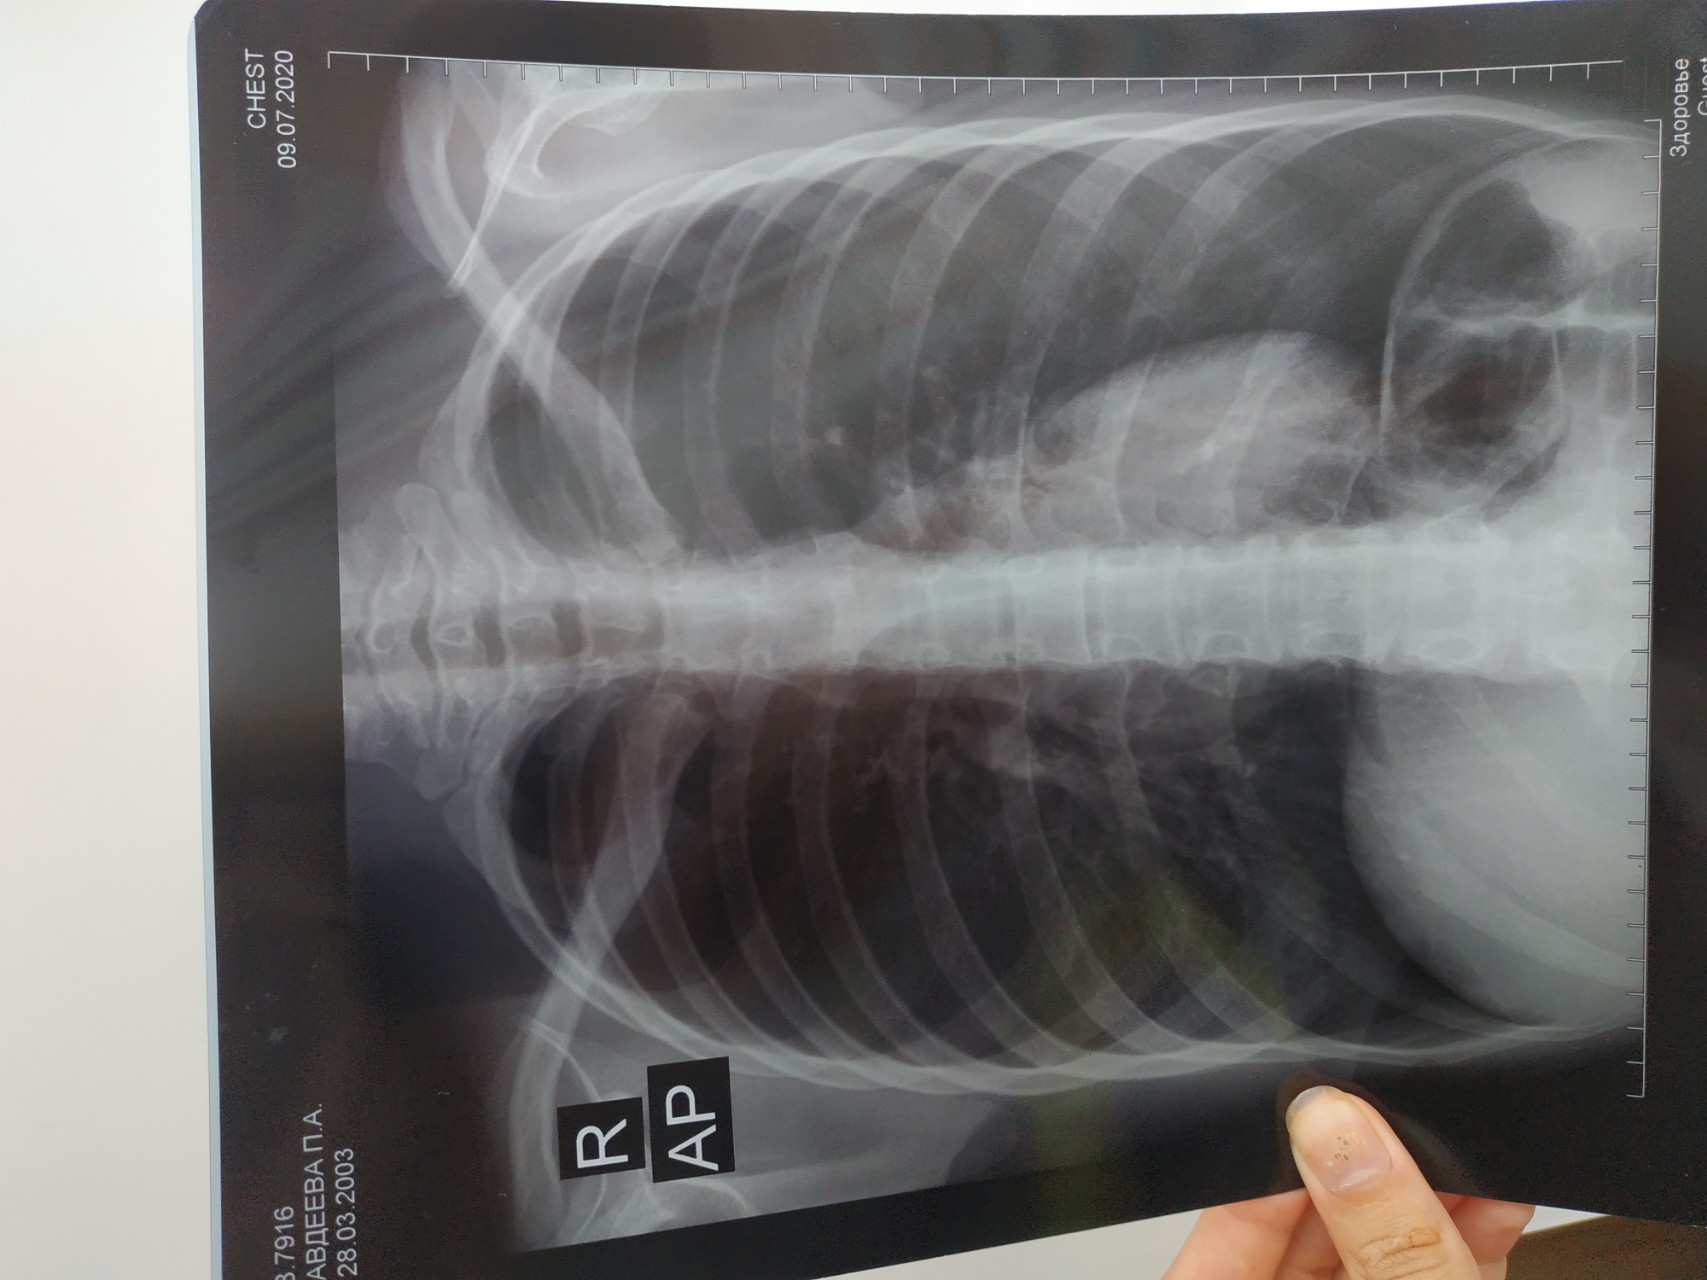

Рентген здоровых легких: примеры снимков и советы

Раздел: Сокровищница опыта